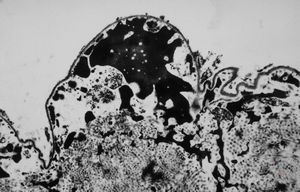

F,17y. | dystrophic calcification in a scar

M,63y. | dystrophic calcification in plexus chorioides

M, | dystrophic calcification and malaric pigment - brain